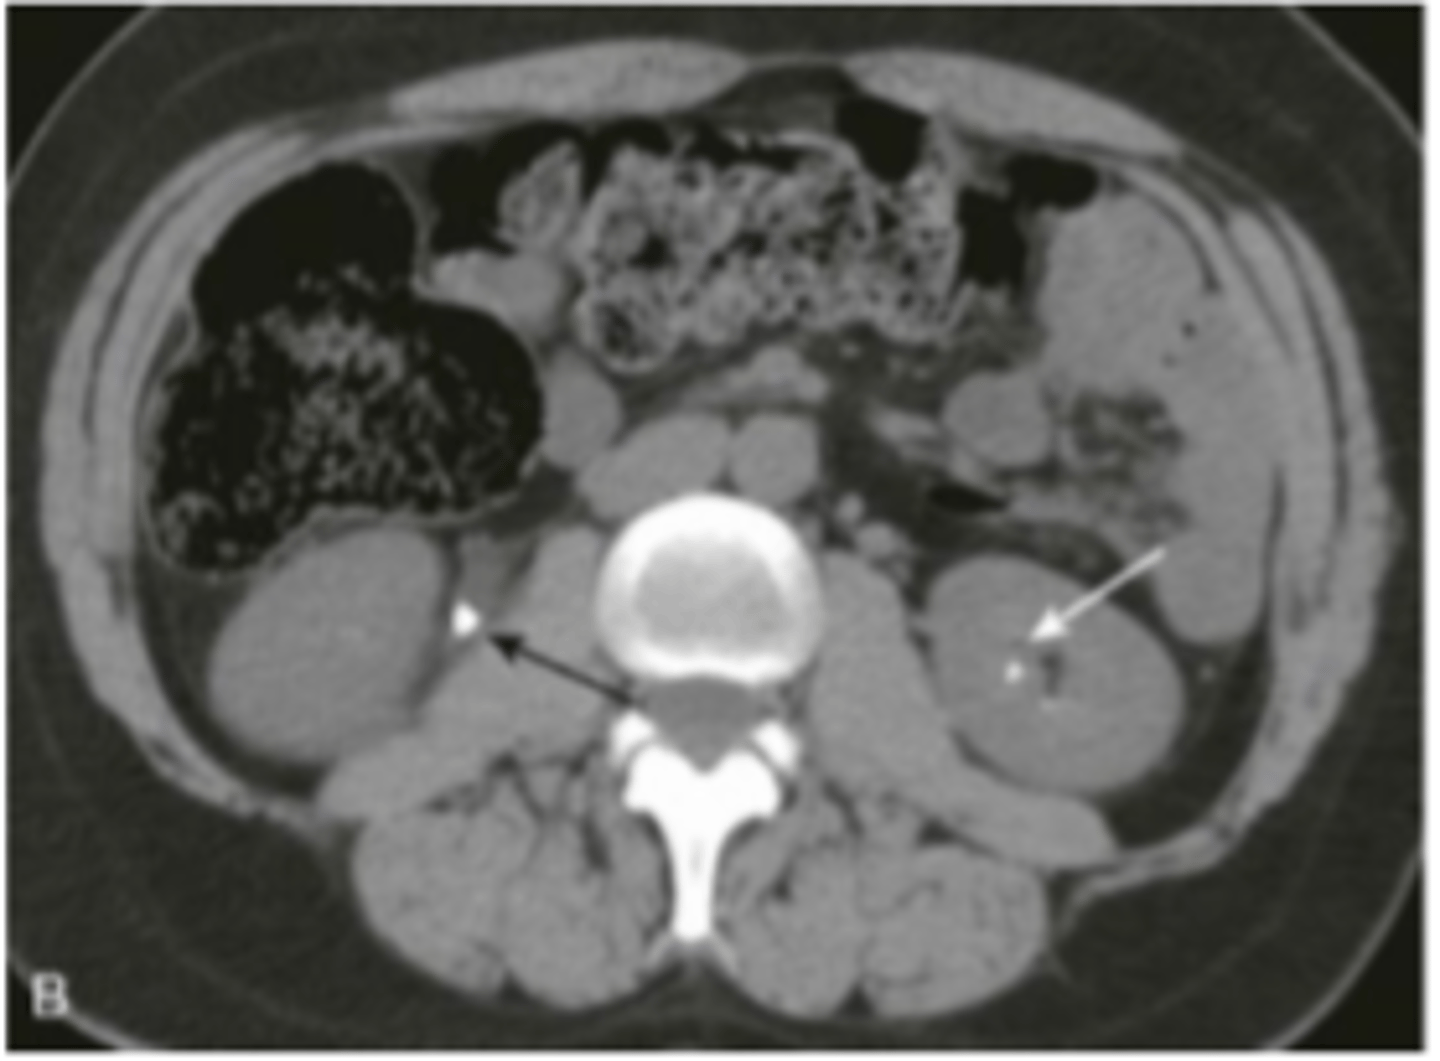

renal imaging

xray (IV pyelography)- mainly replaced by US and CT

US- size, symmetry, lesions, kidney stones, obstructions, hydronephrosis

CT- characterize US abnormalities, study of choice for nephrolithiasis, trauma

MRI- renal cell cancer, mass

renal calculi

stone in R ureter, stone in L kidney